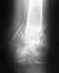

Мы сняли гипсовую повязку - состояние ухудшилось,в приложенном файле ренгтгеннограмма.

Что нам делать дальше?